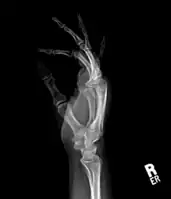

| Bizarre parosteal osteochondromatous proliferation, middle finger | |

Medical imaging usually shows a well-defined wide-based bony growth on the surface of bone.[5] It can be pedunculated and irregular, giving it a "bizarre" appearance, and is not connected to underlying bone.[2]

X-ray hand, BPOP 2nd metacarpal

X-ray hand, BPOP 2nd metacarpal (side view)